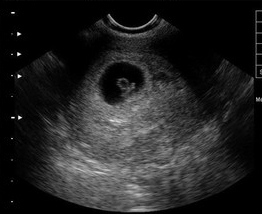

【3】B超检查

[早孕结果]:同房后20天左右(医院检查,可信度高,可判断是否为宫外孕)

红房子指出,B超检查也能确定是宫外孕还是宫内妊娠,胚胎是否存活,这个是其他检查无法比拟的优点。